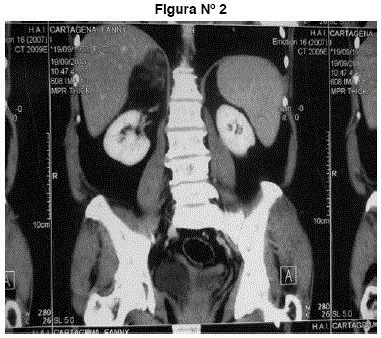

TAC abdomen y pelvis: tumor suprarrenal derecho heterogéneo redondeado, hipodenso con coeficiente de atenuación -38 UH grasa. Mide 66 mm. No adenopatías, no líquido libre, no otros tumores. Imágenes 1 y 2.

Figuras N° 1 y N° 2. Tumor suprarrenal derecho heterogéneo redondeado, hipodenso con coeficiente de atenuación -38 UH grasa. Mide 66 mm. No adenopatías, no líquido libre, no otros tumores.